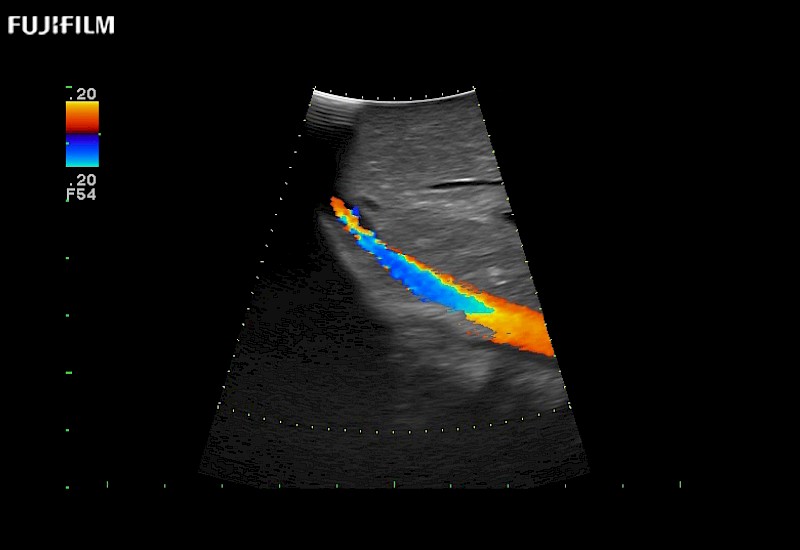

Our dedication to Laparoscopic Surgery allows us to offer superior image quality, outstanding system reliability and intuitive use of cutting edge technology.

The ARIETTA 750 incorporates all of the proven technologies and functions that medical professionals have come to expect from Fujifilm Healthcare.

ARIETTA 750 is the definitive diagnostic ultrasound solution for any clinical setting - Private Office, Imaging Center, or Hospital. The ARIETTA platform provides the ultimate in clinical performance with its state-of-the-art features and large user-friendly display.